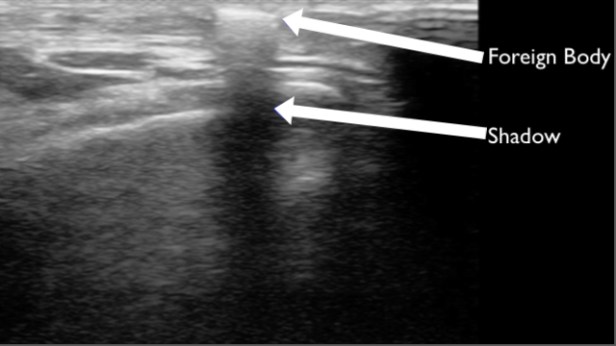

Patient’s history for retained foreign bodies (FB) can be misleading. Many times patients may believe they have a retained FB, but it was just a puncture wound. Other times it may not be clear what type of FB is present and X-ray will miss any non radiopaque FBs. FBs can cause significant pain and can be a source of infection, especially organic FBs. Blind attempts at removal can lead to iatrogenic injury and have poor success rates unless large incisions are created for direct visualization. POCUS can identify organic and nonorganic FBs, identify adjacent anatomy, and guide extraction. FBs typically are hyperechoic on ultrasound and create a clean shadow. Ultrasound guided removal of FBs utilizes a similar technique to other ultrasound guided procedures:

FIGURE 13. SUPERFICIAL FOREIGN BODY IDENTIFIED AS A HYPERECHOIC LINEAR STRUCTURE IN THE SUPERFICIAL TISSUE WITH SHADOWING. AFTER REMOVAL IT WAS IDENTIFIED AS A PIECE OF GLASS.